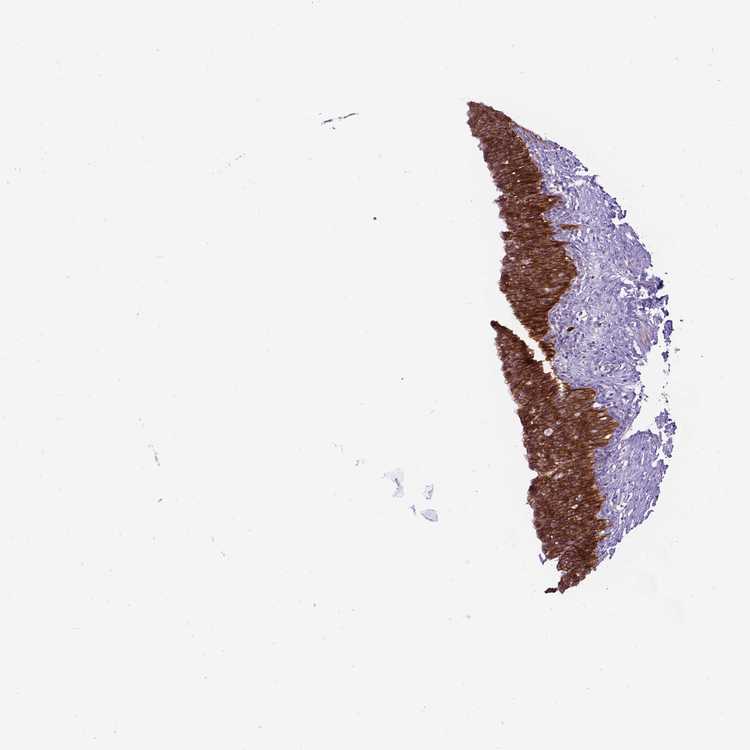

URINARY BLADDER - Antibody stainingi

Antibody staining in the annotated cell types in the current human tissue is reported as not detected, low, medium, or high, based on conventional immunohistochemistry profiling in selected tissues. This score is based on the combination of the staining intensity and fraction of stained cells.

Each image is clickable and will lead to virtual microscopy that enables deeper exploration of all samples and also displays staining intensity scores, fraction scores and subcellular localization as well as patient and tissue information for each sample.

Antibody HPA023626Antibody CAB073536

Urothelial cells HighHigh